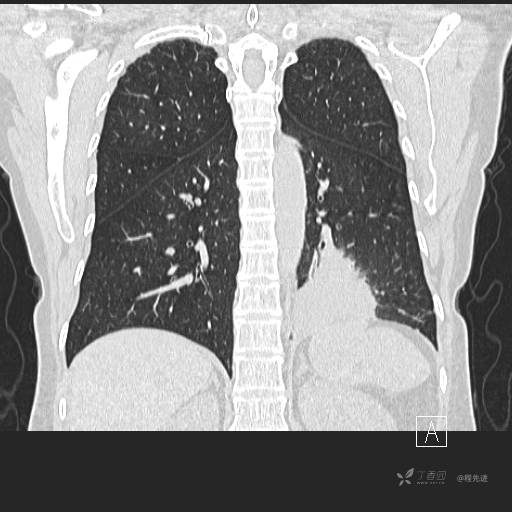

肺窗

冠状位重建

CT值:平扫:31HU,动脉期:74HU,静脉期:84HU